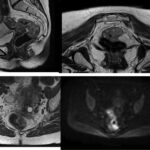

Imágenes de resonancia magnética